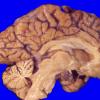

Neuronal Ceroid Lipofuscinosis (NCL) (11)